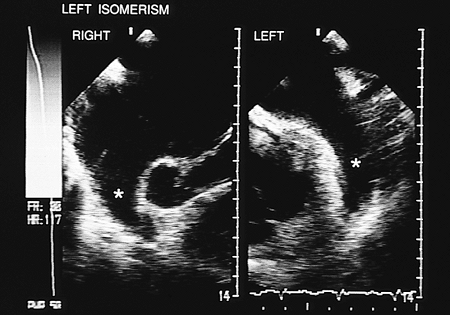

The term atrial isomerism refers to the absence of anatomic lateralization of the atria, which confers ambiguous characteristics on atrial situs. In right isomerism, transesophageal recordings show that both atrial appendages are of right morphology, that is, they are triangular with broad bases (Fig. 8.2.13). In left isomerism, both atrial appendages are elongated with narrow implantations into their atrial cavities (Fig. 8.2.14).

FIGURE 8.2.14. Left atrial isomerism. Transverse plane images. Both atrial appendages (2.14) have a left morphology.